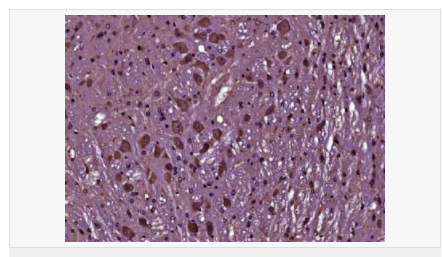

產(chǎn)品應(yīng)用WB=1:500-2000 ELISA=1:5000-10000 IHC-P=1:100-500 IHC-F=1:100-500 Flow-Cyt=1μg/Test IF=1:100-500 (石蠟切片需做抗原修復(fù))

免 疫 原KLH conjugated Synthesised phosphopeptide derived from human Bcl-2 around the phosphorylation site of Thr129:FA(p-T)VV

產(chǎn)品介紹BCL2 is an integral outer mitochondrial membrane protein that blocks the apoptotic death of some cells such as lymphocytes. Constitutive expression of BCL2, such as in the case of translocation of BCL2 to Ig heavy chain locus, is thought to be the cause of follicular lymphoma. Two transcript variants (alpha and beta) produced by alternate splicing, differ in their C-terminal ends. BCL2 suppresses apoptosis in a variety of cell systems including factor-dependent lymphohematopoietic and neural cells. It regulates cell death by controlling the mitochondrial membrane permeability. It appears to function in a feedback loop system with caspases. BCL2 inhibits caspase activity either by preventing the release of cytochrome c from the mitochondria and/or by binding to the apoptosis-activating factor (APAF1). It can form homodimers, and heterodimers with BAX, BAD, BAK and BclX(L). Heterodimerization with BAX requires intact BH1 and BH2 domains, and is necessary for anti-apoptotic activity.